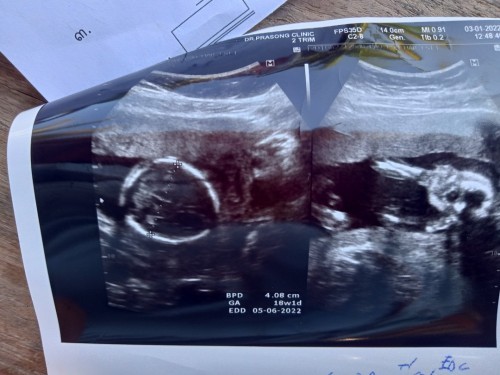

เอาภาพอัลตราซาวด์มาอวดจ้า บ้านนี้แลบลิ้นให้ป้าหมอไป1ที แถมเตะโชว์ไป1ที5555ป้าหมอบอกอาจจะดื้อนะ #ลูกสาว #ท้องแรก